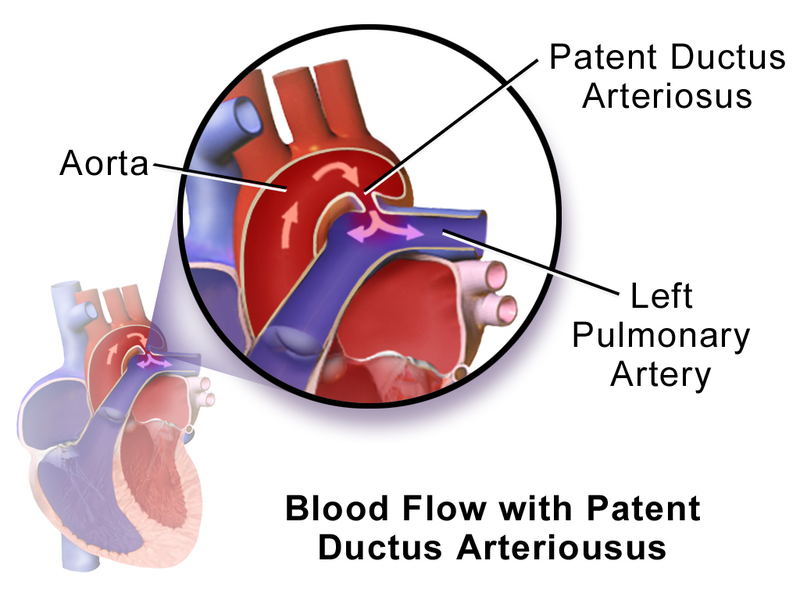

Patent Ductus Arteriosus (PDA)

A patent ductus arteriosus (PDA) results from failure of the ductus arteriosus close.

Patent ductus arteriosus (PDA) is linked to congenital rubella.

Patent ductus arteriosus (PDA) results in a left-to-right shunt between the pulmonary artery and the aorta.

The ductus arteriosus generally diverts blood away from the lungs and toward the aorta during development.

Patent ductus arteriosus (PDA) is typically asymptomatic at birth with a holosystolic ‘machine-like’ murmur.

Patent ductus arteriosus (PDA) may result in lower extremity cyanosis and Eisenmenger syndrome.

Treatment of patent ductus arteriosus (PDA) involves indomethacin, which decreases prostaglandin E1 (PGE1), resulting in PDA closure.

Note that PGE1 maintains patency of the ductus arteriosus.

Prostaglandin E1 (PGE1) can be given to keep a patent ductus arteriosus (PDA) open until a permanent surgical repair is made.